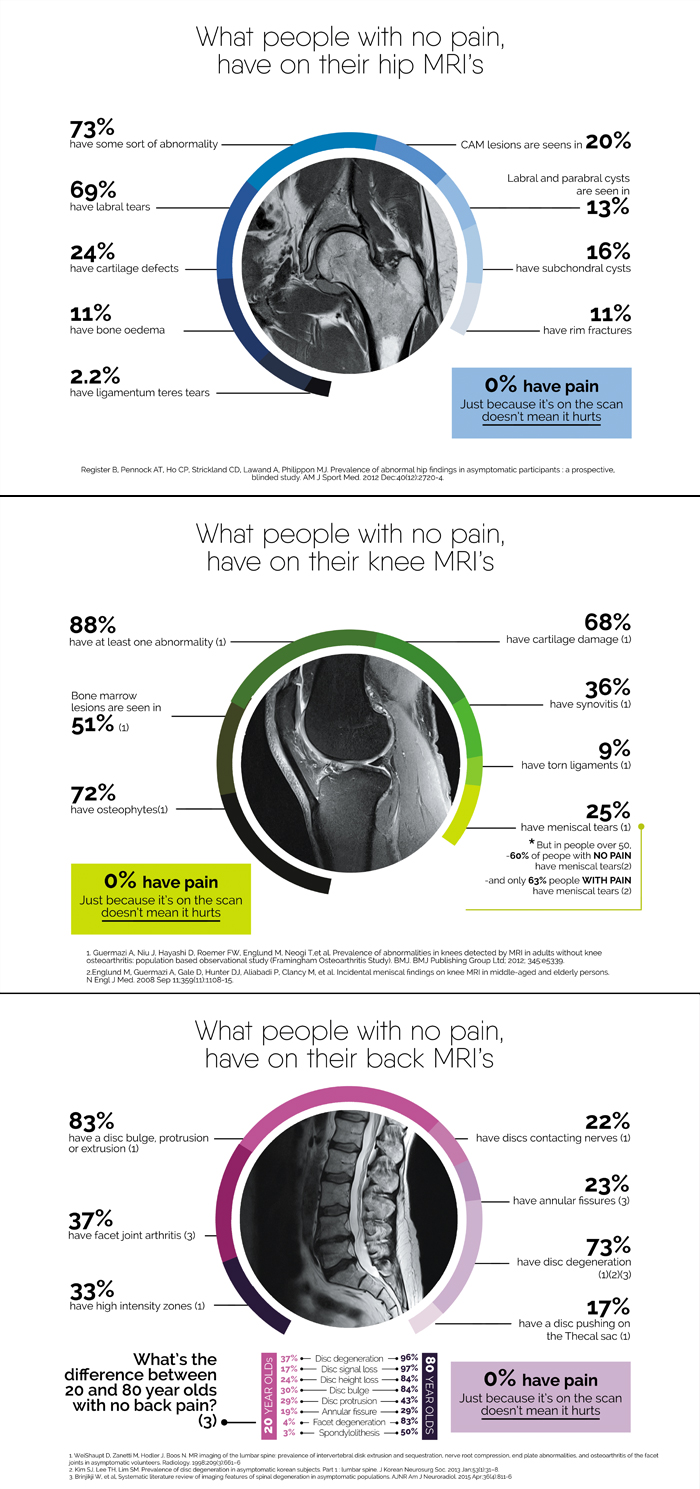

Hi, I have 3 diagrams that I have done that are dodgy, that I need to look good. They need to be high quality to be printed in a magazine for an article I am writing. And of course I need them yesterday. Actually I need them in 8 hours.

Medial Magazine article

Medical

- Must be able to be printed, in a magazine.

MRI Hip Tuesday, 05 April 2016 11:59:12

MRI knee 2 Tuesday, 05 April 2016 11:59:12

MRI knee1 Tuesday, 05 April 2016 11:59:13

MRI SPINE -4 0001 Tuesday, 05 April 2016 11:59:13

MRI SPINE -4 0002 Tuesday, 05 April 2016 11:59:13

MRI Sknee 4 0001 Tuesday, 05 April 2016 11:59:14

MRI hip 5 0001 Tuesday, 05 April 2016 11:59:14

MRI Sknee 5 0001 Tuesday, 05 April 2016 11:59:14